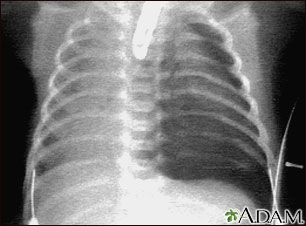

Tests that may be ordered include:

- Chest x-ray